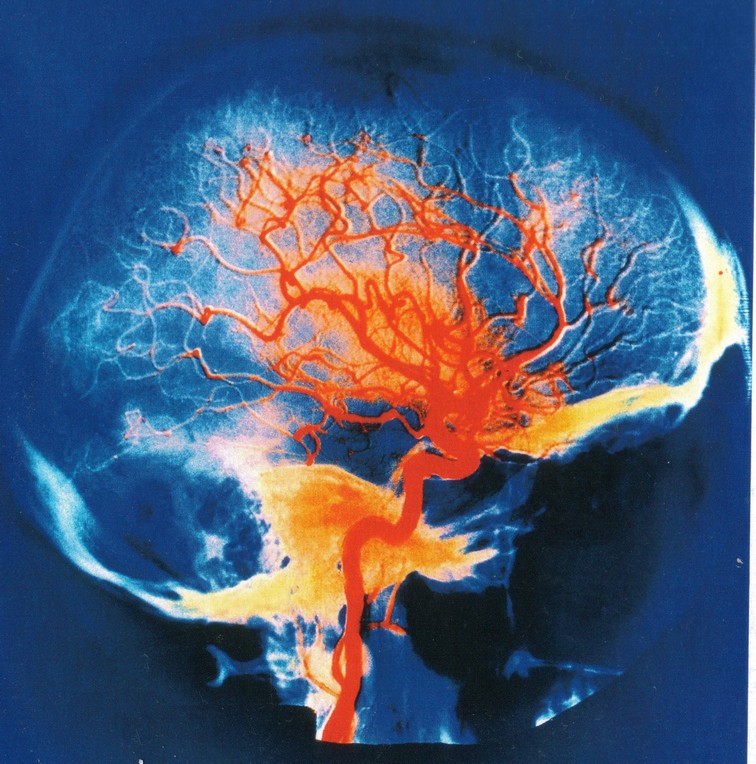

L'IRRIGATION DU CERVEAU